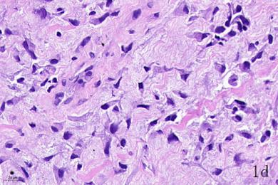

NDN(Necdin)属于黑色素瘤抗原(MAGE)家族,由60多个基因构成共享高度保守的MAGE同源结构域(MHD)[6,7]。最近几年的研究提出NDN是一种新的抑癌基因,其在卵巢癌[8]、乳腺癌[9]和黑色素瘤[10]等的组织和细胞系中低表达,过表达NDN可以抑制其生长,但NDN在骨肉瘤中的作用及机制尚不清楚。为探讨NDN在骨肉瘤中的作用及途径,我们收集了骨肉瘤患者的石蜡标本以及临床信息,对其进行了免疫组化检测及生存分析。通过对骨组织和骨肉瘤HE染色发现,骨组织组,骨密质呈板层状,陷窝中可见骨细胞呈梭形排列( 图1 a 1b) ;骨肉瘤组,瘤细胞呈多角形,核大深染,核分裂多见,瘤细胞呈车辐状排列,瘤细胞间可见少量肿瘤性骨质形成(图1c1d)。同时通过免疫组化发现,NDN表达主要位于细胞的胞核中。NDN在骨肉瘤组织中的表达率为29.4%(15/51)(图1c1d),明显低于瘤旁骨组织阳性表达率80%(8/10)(图1a1b)。